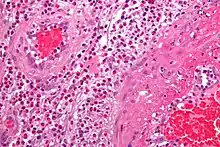

| Vasculitis | Affected organs | Histopathology |

| Cutaneous small-vessel vasculitis | Skin, kidneys | Neutrophils, fibrinoid necrosis |

| Granulomatosis with polyangiitis | Nose, lungs, kidneys | Neutrophils, giant cells |

| Eosinophilic granulomatosis with polyangiitis | Lungs, kidneys, heart, skin | Histiocytes, eosinophils |

| Behçet's disease | Commonly sinuses, brain, eyes and skin; can affect other organs such as lungs, kidneys, joints | Lymphocytes, macrophages, neutrophils |

| Kawasaki disease | Skin, heart, mouth, eyes | Lymphocytes, endothelial necrosis |

| Buerger's disease | Leg arteries and veins (gangrene) | Neutrophils, granulomas |

- The definite diagnosis of vasculitis is established after a biopsy of involved organ or tissue, such as skin, sinuses, lung, nerve, brain, and kidney. The biopsy elucidates the pattern of blood vessel inflammation.